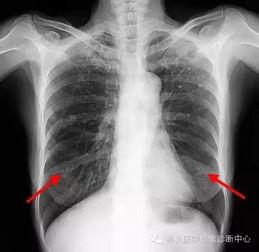

首先,得先弄清楚什么是胸片。胸片,顾名思义,就是通过X射线对人体胸部进行拍摄的一种医学影像检查。它能够清晰地显示出心脏、肺部、纵隔等器官的结构和形态,对于诊断各种胸部疾病有着至关重要的作用。

胸片检查是诊断肺部疾病的重要手段。通过观察肺部影像,医生可以初步判断患者是否患有肺炎、肺结核、肺癌等疾病。

胸片检查还可以用于诊断心脏疾病,如心包积液、心脏增大等。